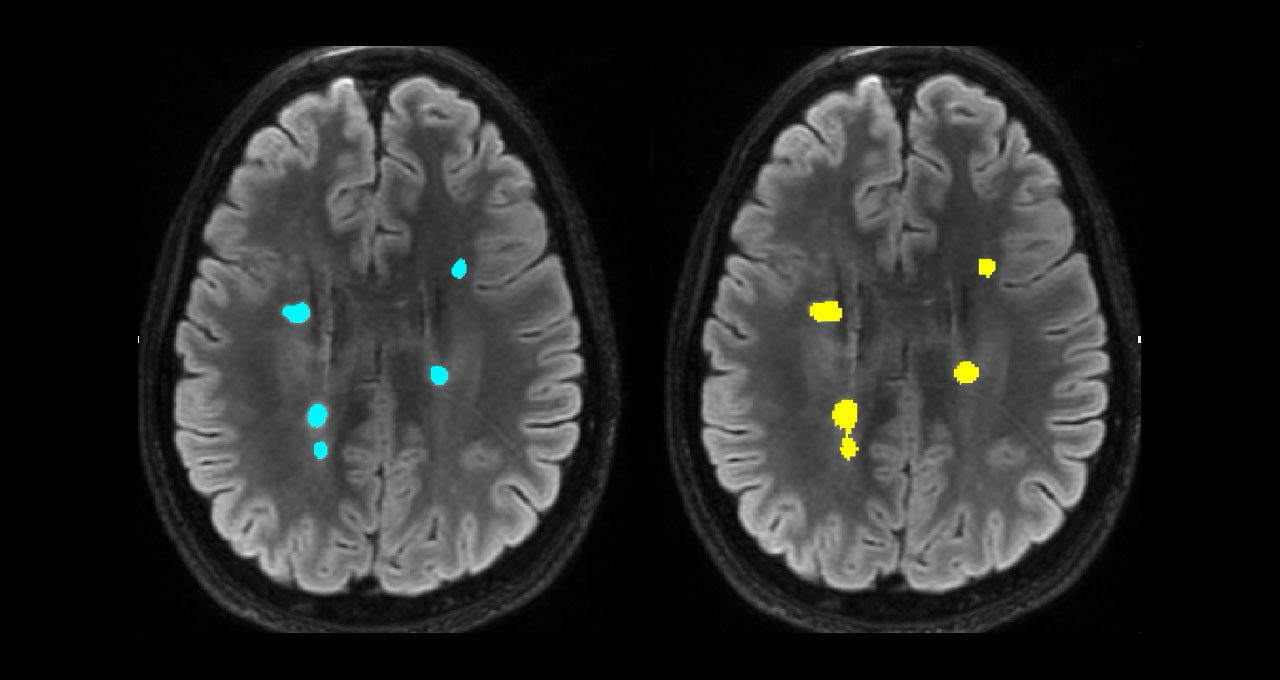

另一個(gè)工具可處理多發(fā)性硬化癥病例的大腦病灶分析。在研究和臨床試驗(yàn)中,影像分析師通常會(huì)分割大腦病灶,并通過(guò)手動(dòng)檢查掃描來(lái)確定其大小,這一過(guò)程要耗費(fèi)長(zhǎng)達(dá) 15 分鐘。

AI 可將確定病灶大小所需的時(shí)間縮短為 3 秒。這就使得這些指標(biāo)也可以用于臨床實(shí)踐,以往由于時(shí)間限制,放射科醫(yī)生通常只通過(guò)眼睛簡(jiǎn)單觀察來(lái)估計(jì)病灶大小。

主圖顯示了多發(fā)性硬化癥病灶分割的并排對(duì)比。左圖顯示的是手動(dòng)病灶分割,右圖顯示的是全自動(dòng)病灶分割。圖片由悉尼神經(jīng)影像分析中心提供。